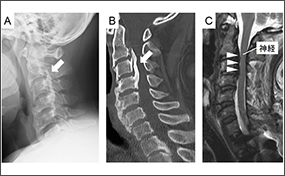

脊柱後縦靭帯骨化症の発症原因の一端を解明 -日本人を対象とした世界最大規模のゲノム解析-(共同プレスリリース)

理化学研究所の小池良直客員研究員(北海道大学大学院医学研究院整形外科学教室)、寺尾知可史チームリーダー(静岡県立総合病院免疫研究部長、静岡県立大学特任教授)らの共同研究グループは、日本人を対象にした大規模なゲノムワイド相関解析(GWAS)を行い、脊柱後縦靭帯骨化症(ossification of posterior longitudinal ligament:OPLL)の発症に関わるゲノム上の新しい疾患感受性領域(遺伝子座)を同定しました。